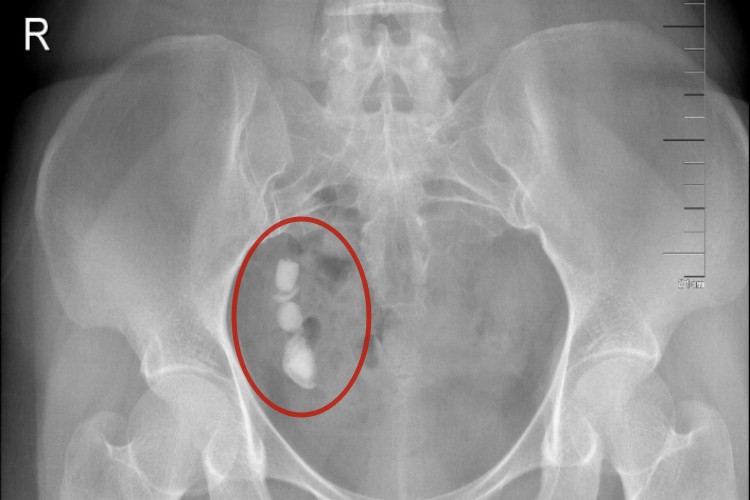

输尿管结石

输尿管结石也可引起阵发性发作的肾绞痛,表现为腰部或上腹部剧烈疼痛,并沿着输尿管走向放射至同侧腹股沟,还可累及同侧睾丸或阴唇,并伴发镜下血尿、恶心、呕吐、尿频、尿急、尿痛、寒战、发热、腰痛等症状。